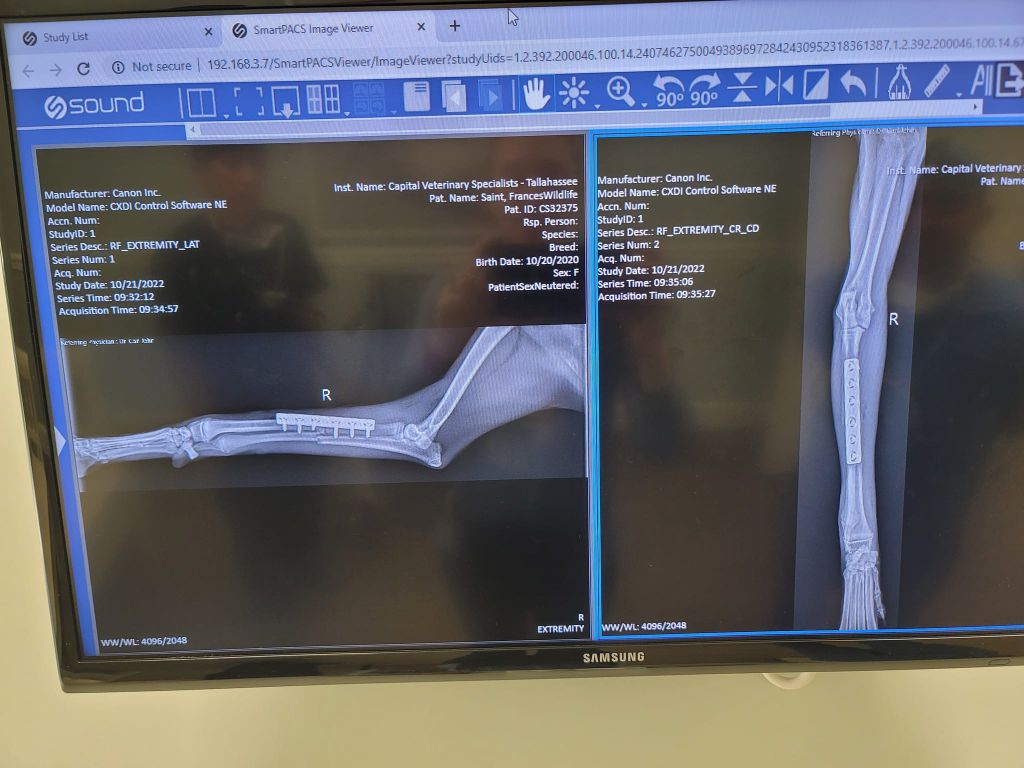

Veterinary Technician Shaun Hall at Allied Veterinary Hospital assists while the leg is splinted.

Rescuers told The Miami Herald that the animal was rescued just in time and had suffered fractures to her right front radius and ulna.